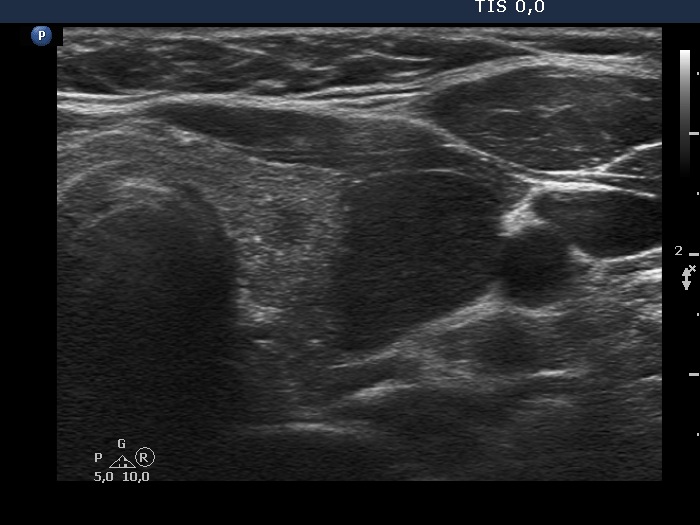

100 consecutive cases of papillary cancer - case 076 (ultrasonographic picture 5)

Left lobe, another transverse view. The nodule shows abutting contours, the perimeter abutment is between 25 and 50%.